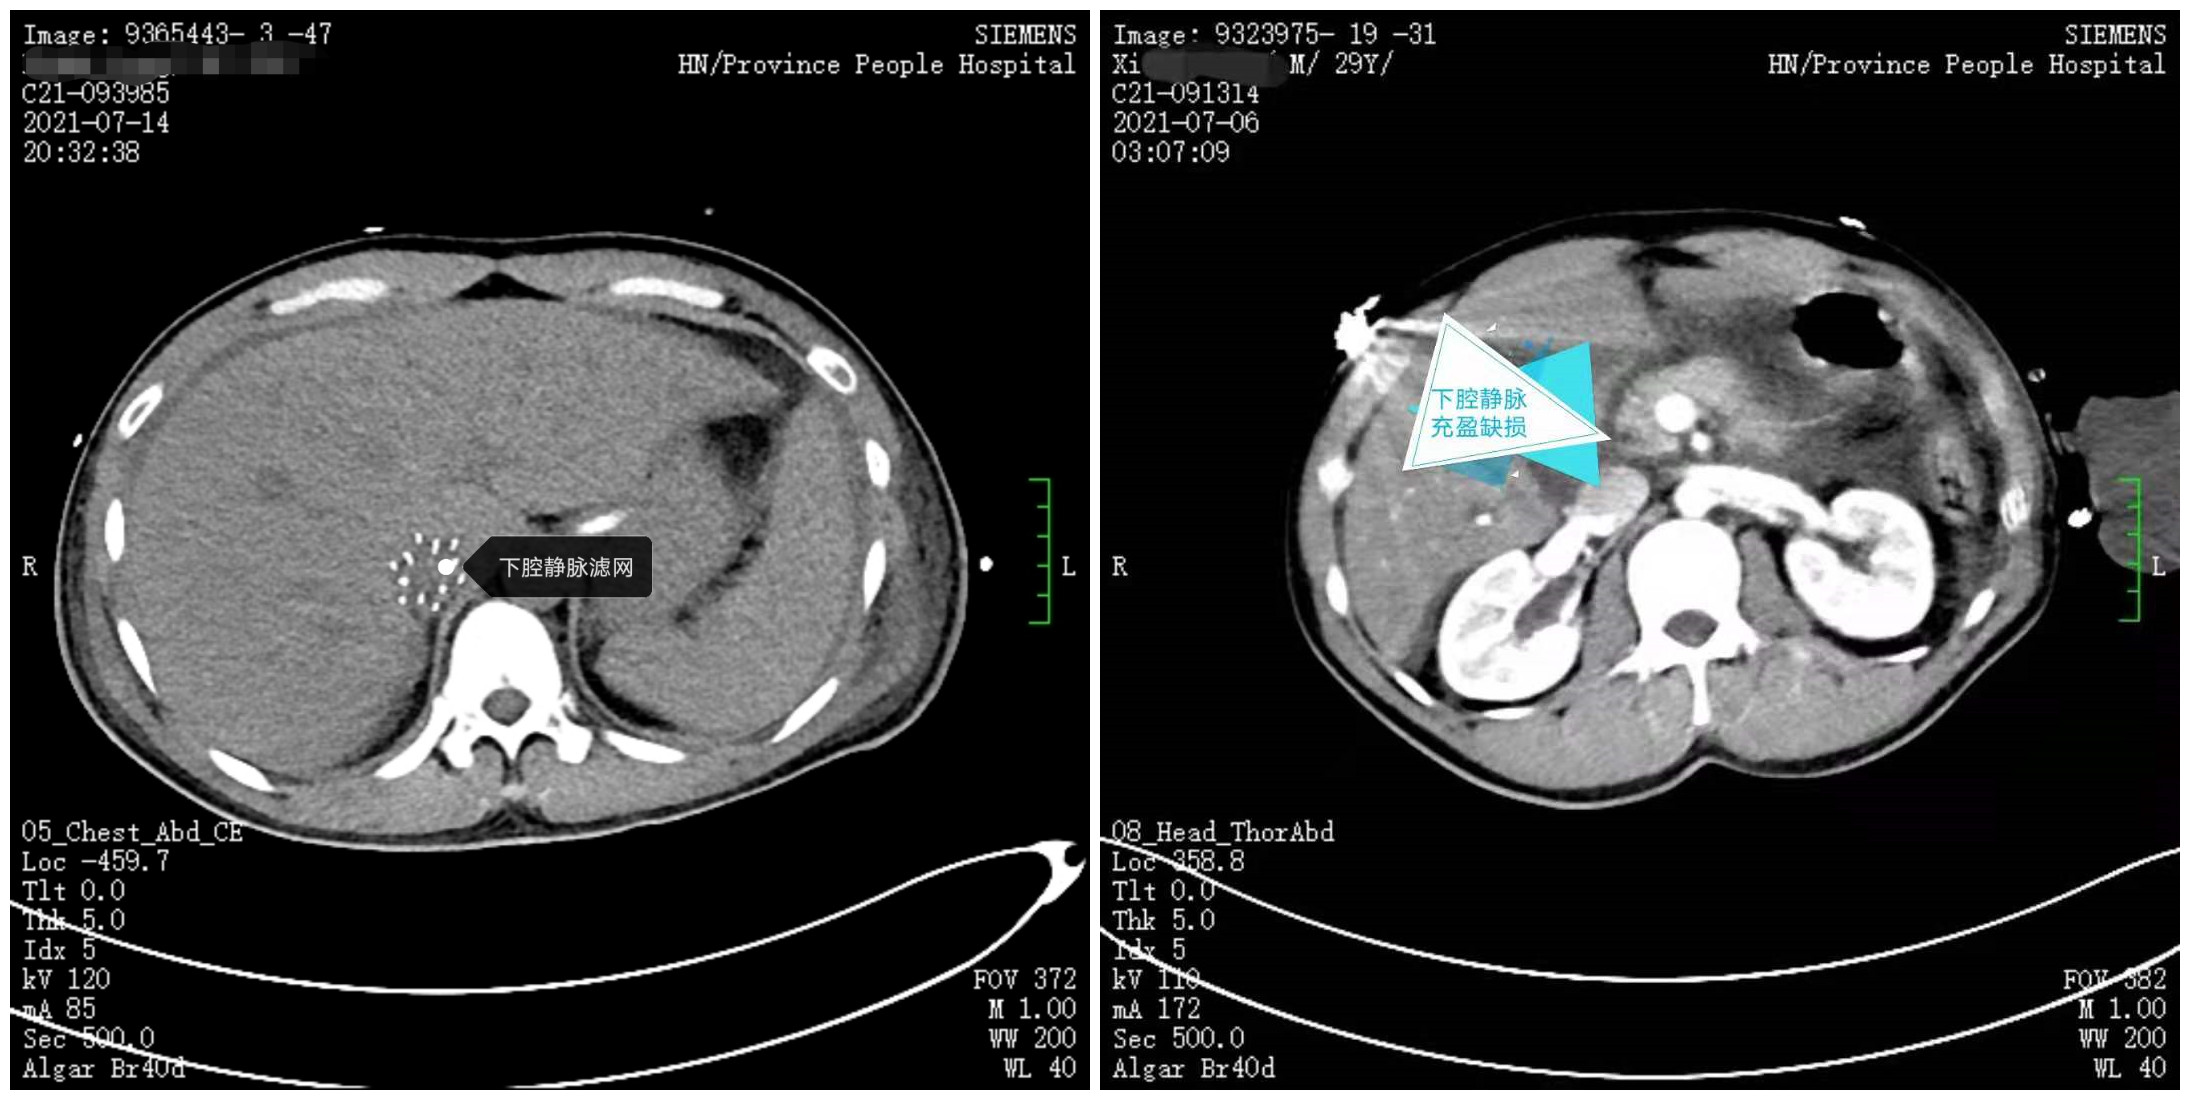

下腔静脉缺损、下腔静脉滤网植入术后

最终小何被收入急诊重症病房(EICU)进行综合管理治疗,介入血管外科为其实施了下腔静脉滤网植入+肝右动脉栓塞术,先期止血和解决下腔静脉血栓脱落问题,再由心内科实施冠脉内溶栓+抽血栓,确保其心脏血供,维持心肌功能,后期由李想副主任医师带领创伤小组进行围手术期的综合管理和治疗,解决抗凝与止血的平衡问题。